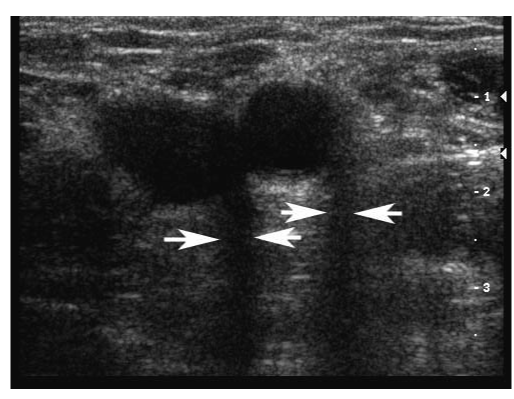

Acoustic enhancement seen distal to a low attenuating structure.

_page_16.png?sfvrsn=4386c723_2)

Acoustic shadow seen distal to a high-attenuating structure.

_page_17.png?sfvrsn=a4a59d32_2)